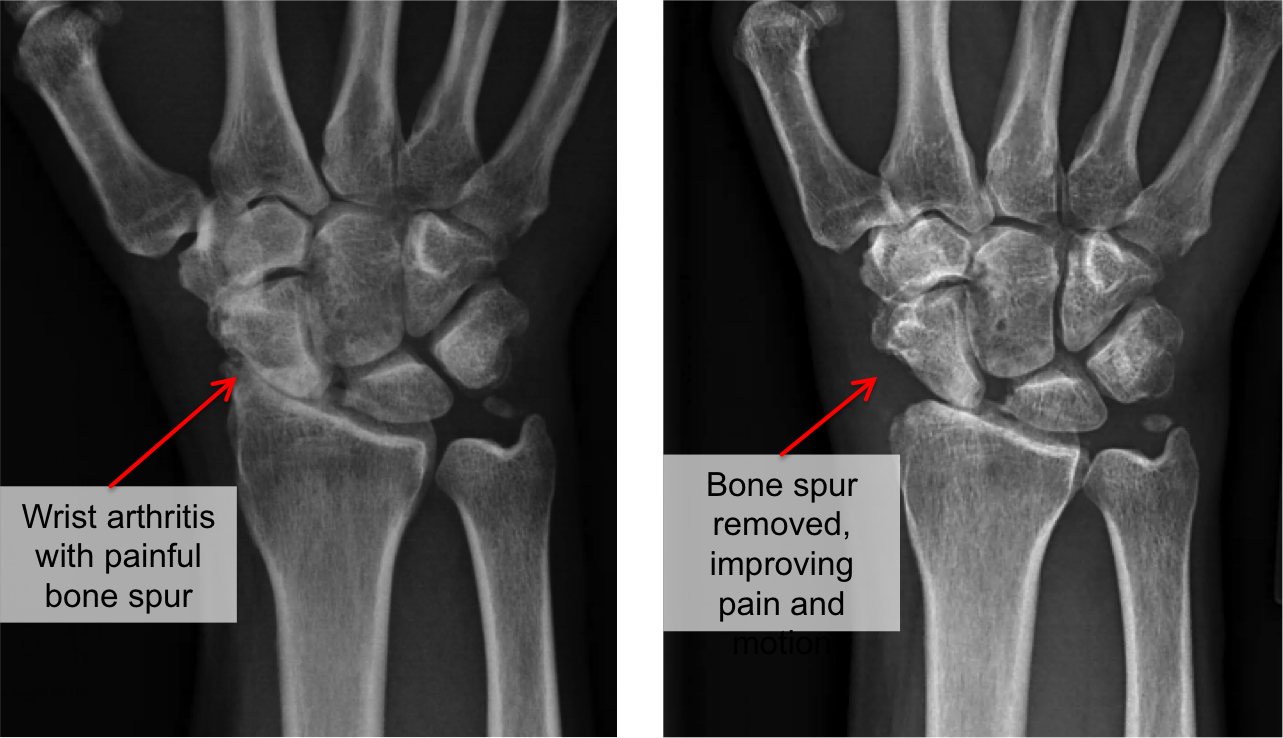

Wrist Arthritis Raleigh Hand Surgery — Joseph J. Schreiber, MD

From www.schreibermd.com

Wrist Arthritis Raleigh Hand Surgery — Joseph J. Schreiber, MD Arthritis In Your Wrist Your wrist is made up of many small joints, and inflammation in these areas can be a sign of arthritis. After the forearm there are two rows of. The base of your thumb, your knuckles, second joint and top joint of your fingers are common sites for hand arthritis. If you’ve been experiencing pain in your wrist,. Published 08/20/19 by. Arthritis In Your Wrist.

Wrist Arthritis Raleigh Hand Surgery — Joseph J. Schreiber, MD Arthritis In Your Wrist If you’ve been experiencing pain in your wrist,. Osteoarthritis is a degenerative joint disease that involves the gradual wear and tear of cartilage, a tough but flexible tissue that covers the ends of the bones in a joint. Published 08/20/19 by stacey feintuch. Arthritis attacks your bones by destroying the cartilage, causing your. There are several types of arthritis that. Arthritis In Your Wrist.